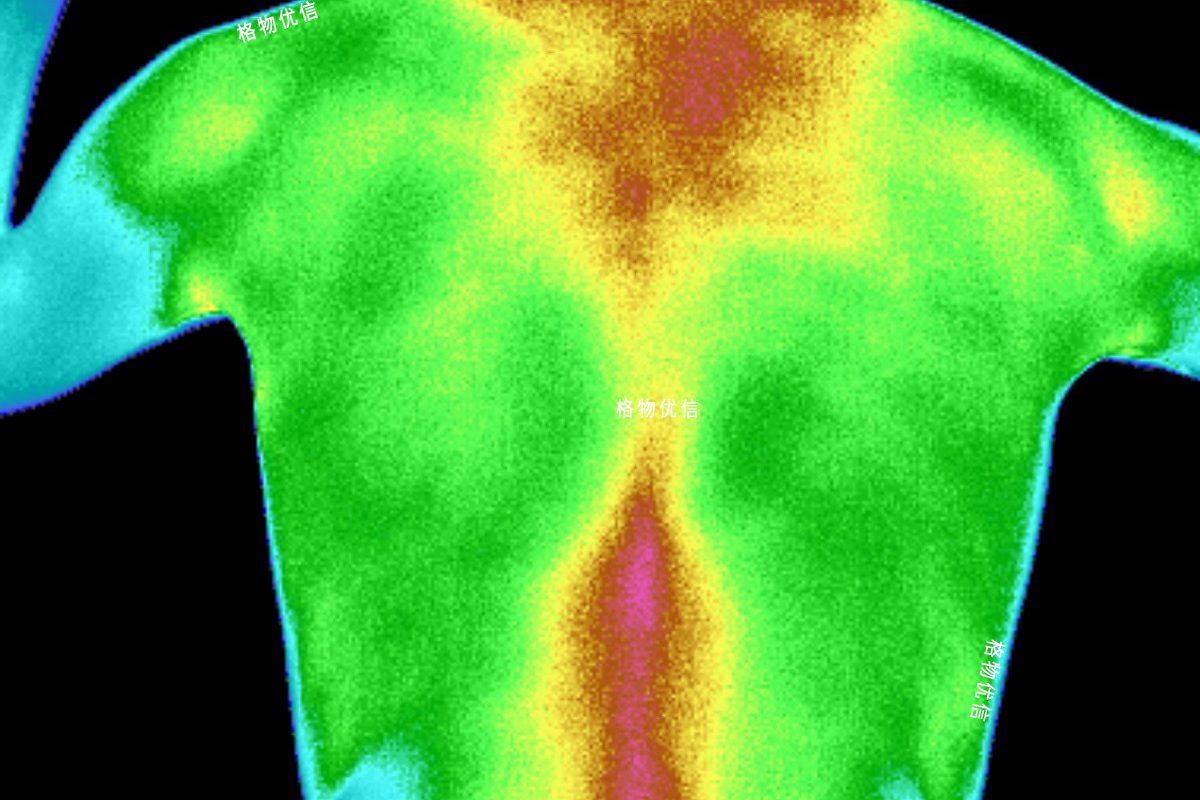

隨著紅外技術的不斷發展,紅外熱像儀逐漸被應用于越來越多的民生行業,吃、穿、住、行無所不在,但是微米級小目標通常…